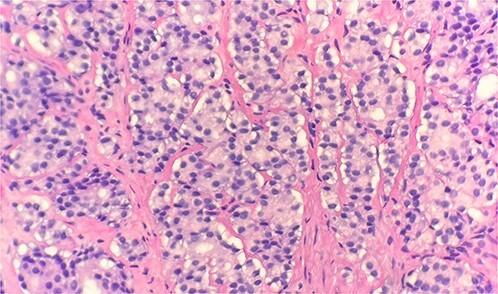

Prostate cancer is the most common cancer among men, with the most common metastatic sites in bone, regional lymph nodes, liver and thorax. It is most commonly diagnosed in the early stages with clinical findings of enlarged prostate on digital rectal exam and positive prostate specific antigen. Distant metastases associated with prostate cancer commonly occur to bone. It is imperative to be cautious in assuming primary breast, lung or head and neck malignancy in patients presenting with lymphadenopathy in the upper aerodigestive pathways. Cervical lymphadenopathy due to prostate cancer is becoming more prevalent since previously reported. Here we present a case of prostate cancer recurrence found through metastasis to supraclavicular lymph nodes and we also highlight homeobox protein CDX2 as a potential clinico-pathological marker in metastatic prostate cancer.

前列腺癌是男性中最常见的癌症,最常见的转移部位是骨骼、区域淋巴结、肝脏和胸部。其最常在早期通过直肠指检发现前列腺肿大及前列腺特异性抗原呈阳性的临床表现而被诊断出来。与前列腺癌相关的远处转移通常发生在骨骼。对于上呼吸道消化道出现淋巴结病的患者,在假设其为原发性乳腺癌、肺癌或头颈部恶性肿瘤时必须谨慎。自先前报道以来,因前列腺癌导致的颈部淋巴结病正变得越来越普遍。在此,我们报告一例通过锁骨上淋巴结转移发现的前列腺癌复发病例,并且我们还强调了同源盒蛋白CDX2作为转移性前列腺癌潜在的临床病理标志物。